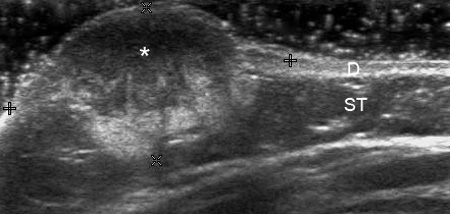

Диагностика гемангиом производится на основании расспроса о времени появления опухоли, данных объективного осмотра, при необходимости выполняются дополнительные исследования, такие как допплерография, МРТ, компьютерная томография.

Гемангиома

Удаление гемангиомы лазером заключается в применении определенного количества лазерных вспышек, направленных на гемангиому. Излучение, генерируемое лазером, хорошо поглощается оксигемоглобином, находящимся в сосудах гемангиомы. Оксигемоглобин, в свою очередь, нагревает эндотелий сосудов и вызывает его разрушение. Это приводит к прекращению кровотока в сосудах, последующему их «склеиванию», и уменьшению размеров самой гемангиомы.